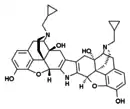

The pharmacodynamic response to an opioid depends upon the receptor to which it binds, its affinity for that receptor, and whether the opioid is an agonist or an antagonist. For example, the supraspinal analgesic properties of the opioid agonist morphine are mediated by activation of the μ1 receptor; respiratory depression and physical dependence by the μ2 receptor; and sedation and spinal analgesia by the κ receptor. Each group of opioid receptors elicits a distinct set of neurological responses, with the receptor subtypes (such as μ1 and μ2 for example) providing even more [measurably] specific responses. Unique to each opioid is its distinct binding affinity to the various classes of opioid receptors (e.g. the μ, κ, and δ opioid receptors are activated at different magnitudes according to the specific receptor binding affinities of the opioid). For example, the opiate alkaloid morphine exhibits high-affinity binding to the μ-opioid receptor, while ketazocine exhibits high affinity to ĸ receptors. It is this combinatorial mechanism that allows for such a wide class of opioids and molecular designs to exist, each with its own unique effect profile. Their individual molecular structure is also responsible for their different duration of action, whereby metabolic breakdown (such as N-dealkylation) is responsible for opioid metabolism.

Several semi-synthetic opioids were developed in Germany in the 1910s. The first, oxymorphone, was synthesized from thebaine, an opioid alkaloid in opium poppies, in 1914.[228] Next, Martin Freund and Edmund Speyer developed oxycodone, also from thebaine, at the University of Frankfurt in 1916.[229] In 1920, hydrocodone was prepared by Carl Mannich and Helene Löwenheim, deriving it from codeine. In 1924, hydromorphone was synthesized by adding hydrogen to morphine. Etorphine was synthesized in 1960, from the oripavine in opium poppy straw. Buprenorphine was discovered in 1972.[228]

Morphinan derivatives